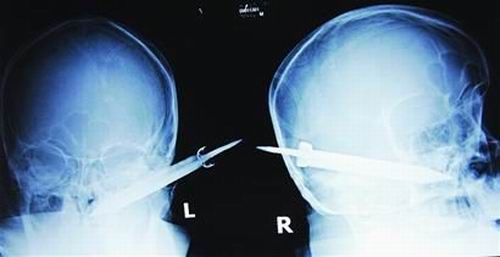

經(jīng)過檢查,醫(yī)生說這把長(zhǎng)有10厘米左右的刀,從右耳窩上前方直接刺進(jìn)了鼻腔,離頜內(nèi)大動(dòng)脈很近,刀卡在了骨頭中,要取出這把刀最怕大出血,萬(wàn)幸的是這把三棱刀并沒有傷及大腦。

截至昨晚11時(shí)30分,患者頭部刀經(jīng)手術(shù)已取出,生命體征平穩(wěn)。(芮瀟瀟)